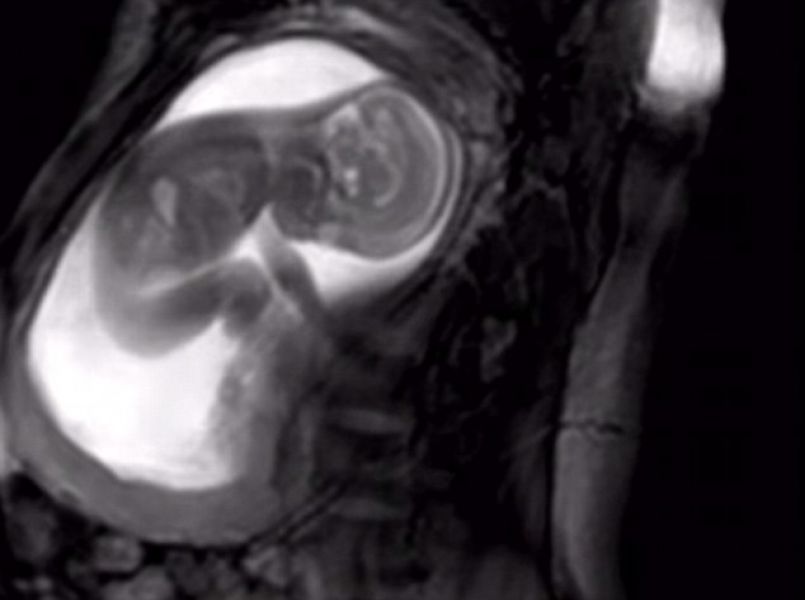

Aanstaande ouders kunnen binnenkort hun ongeboren baby’s zien rekken, strekken, wiebelen, slikken en zelfs aan de navelstreng trekken dankzij een nieuwe MRI-scan.

Maar dankzij jarenlang onderzoek (en zo’n twaalf miljard euro) zijn Londense wetenschappers erin geslaagd een nieuwe manier van prenataal onderzoek te introduceren. Met de nieuwe MRI-scan is het mogelijk om glasheldere beelden van je ongeboren uk te zien.

Niet alleen leuk voor de ouders (want hóe geweldig is het om je kleintje al zo duidelijk te zien wiebelen in je buik?!), maar ook handig voor de medische wetenschap. Je ongeboren kind kan door deze nieuwe technologie nog beter gecheckt worden, waardoor een 20-wekenecho nog duidelijker wordt.

In dit korte filmpje, gemaakt door het iFIND-project, is te zien wat een baby met twintig weken zwangerschap uitspookt in de baarmoeder. Je kunt het kindje hoe het kindje met de navelstreng speelt, zich uitrekt en zijn hoofdje draait.